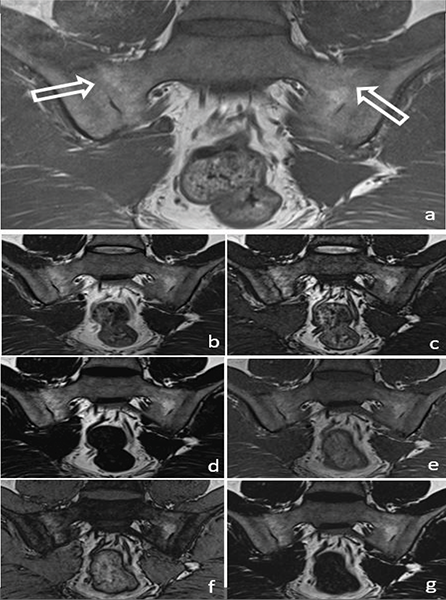

Figure 3

A 34‑year‑old male patient with ankylosis (arrow) in both sacroiliac joints on a T1W image (a) (arrows). Ankylosis can be easily seen in the T2W Dixon IP (b), T2W Dixon OP (c), T2W Dixon FO (d), T1W Dixon IP (e), T1W Dixon OP (f) and T1W Dixon FO (g) images shown in the figure.